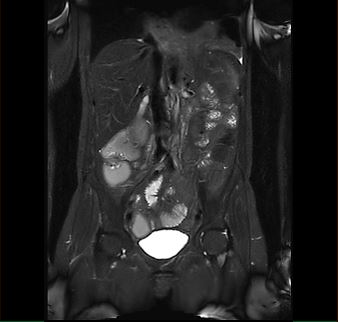

Beispiele von MRT-Abdomen Aufnahmen